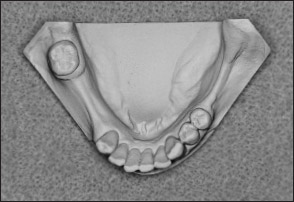

Fig 1-11 Maxillary Kennedy Class I arch.

Fig 1-12 Mandibular Kennedy Class I arch.